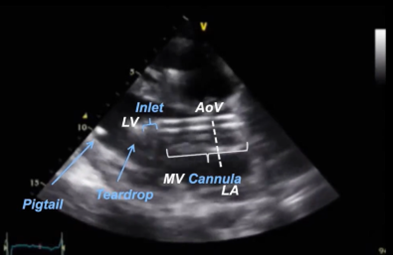

On imaging, the Impella catheter appears as a bright linear echogenic structure crossing the aortic valve. The inlet is typically visualized just apical to the mitral valve plane and often displays a “teardrop sign”—an echolucent space representing blood being drawn into the pump.² The outlet should be in the proximal ascending aorta, not retracting into the valve or extending excessively. The pigtail tip (for Impella 2.5 and CP), visible as a curled loop extending toward the apex, helps reduce myocardial trauma and aids device orientation. Color doppler may reveal continuous flow from the LV to the aorta through the device when the device is properly placed and functioning. Figure 1 shows an example of incorrect positioning, as the inlet is located in the LV myocardium, while Figure 2 demonstrates the correct positioning of the Impella. The inlet positioning should be approximately 3.5–4 cm from the aortic annulus for Impella CP and 5.0, and 5 cm from the aortic annulus for the Imeplla 5.5.²

Figure 2: Proper Impella Placement. This figure shows correct placement of the impella device, with the inlet in the mid LV cavity approximately 3.5cm from the aortic valve annulus.